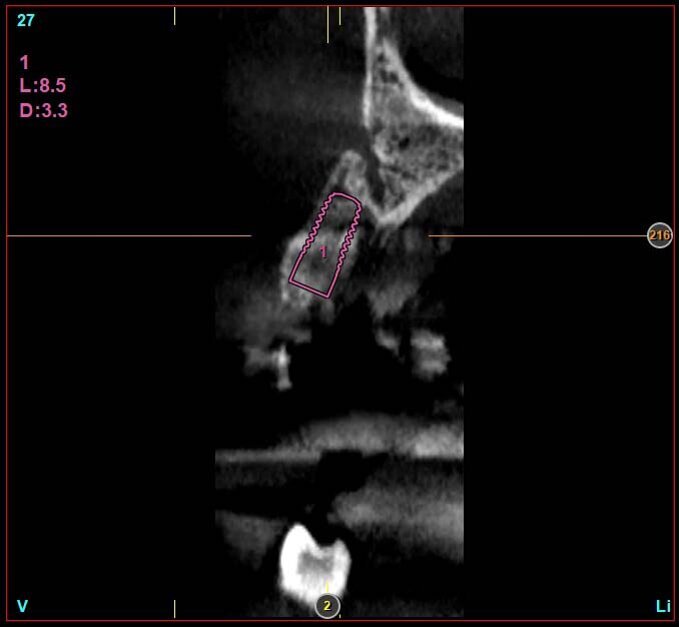

Le corone sui denti 1.3 e 1.4 furono rimosse, il dente 1.3 fu estratto e l’alveolo fu riempito con una membrana di PRGF ottenuta tramite centrifugazione del sangue della paziente con il sistema Endoret e un provvisorio fu consegnato sui denti 1.3 e 1.4 (Fig. 5, 6). Dopo otto settimane fu eseguita una nuova cone-beam e la chirurgia fu pianificata (Fig. 7). Si eseguì un lembo a tutto spessore, fu eseguita l’osteotomia e fu inserito un impianto BTI Core 3.5 × 8.5. Un pilastro Unit fu avvitato e un tappo di guarigione fu applicato. L’osso ottenuto dalla fresatura mescolato con una membrana di PRGF fu applicato sul lato palatale per compensare una piccola deiscenza, una seconda membrana fu applicata sopra l’osso circostante e un innesto di tessuto connettivo prelevato dalla tuberosità fu suturato vestibolarmente per ricreare la bozza canina. Punti di sutura staccati furono eseguiti con un filo in PTFE (Figg. 8-11). Dopo quattro mesi il provvisorio fu rimosso e i tessuti apparivano sani e con un buon spessore di tessuto connettivo vestibolare per garantire la stabilità nel tempo del risultato. Fu eseguita un’impronta con la tecnica del cucchiaio aperto e dopo due settimane furono consegnate una corona in zirconio cementata sul dente 14 ed una avvitata sul denta 1.3. Il profilo di emergenza della corona sull’impianto appariva ideale. Purtroppo, a causa della mancanza del picco osseo sul versante distale del dente 1.2, non si ottenne una papilla di altezza adeguata. Ciononostante la paziente si disse soddisfatta del risultato e rifiutò ulteriori terapie per correggere il difetto residuo (Figg. 12-15).

La presenza di difetti ossei dopo l’apicectomia eseguita sul dente 1.2 fece decidere di non eseguire un impianto post-estrattivo immediato. La presenza dei difetti ossei e la presenza di cicatrici a carico dei tessuti molli rendeva di difficile esecuzione procedure di GBR che richiedessero il rilascio dei lembi. Si decise pertanto di compensare la perdita di tessuto vestibolare con un innesto di tessuto connettivo. L’inserimento di un impianto di 8,5 mm permise di ottenere un asse di inserzione ideale e di avere il foro di fuoriuscita della vite collocato palatalmente senza il bisogno di correggere l’angolazione. Tutto ci. ha permesso di eseguire procedure chirurgiche e protesiche semplici e ben sopportate dalla paziente e soprattutto di raggiungere un buon risultato estetico e funzionale.